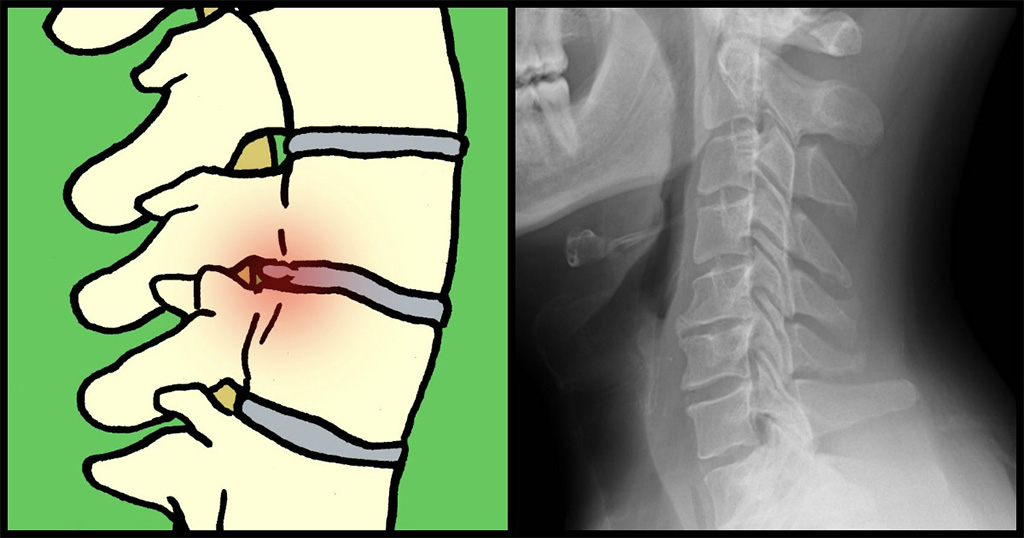

Τι είναι η δισκοπάθεια;

Η δισκοπάθεια εμφανίζεται όταν ο μαλακός ιστός που διαχωρίζει τους σπονδύλους σπάει, προκαλώντας πολύ πόνο και δυσφορία, σύμφωνα με τη Κλινική Μέιο.Αυτό μπορεί να συμβεί σε οποιοδήποτε μέρος της σπονδυλικής στήλης, όμως είναι συχνότερη η εμφάνισή του στη μέση (οσφυϊκή χώρα) ή τον αυχένα.